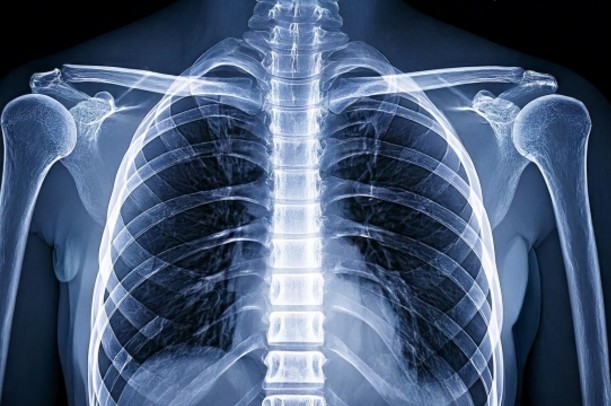

呼吸をするたびに背中が痛むのは、「呼吸動作で胸郭(きょうかく)が動くから」です。

息を吸うと肋骨が外側・上方向へ広がり、それに連動して背中の筋肉や関節、神経が引き伸ばされます。

このとき、筋肉の緊張・神経の圧迫・関節のこわばりなどがあると、動きに合わせて痛みが出る仕組みになっています(引用元:Awataおじ公園整骨院「肋間神経痛とは?症状・特徴」)。

背中は、筋肉・骨格・神経・内臓が密接に関わる部位です。

息を吸うと背中が痛むのは、「肋間神経痛」「筋肉の緊張」「胸膜や肺の炎症」など、どれも呼吸に連動して動く構造に問題が起きているからだと考えられています(引用元:rehasaku.net「呼吸と背中の痛みの関係」)。